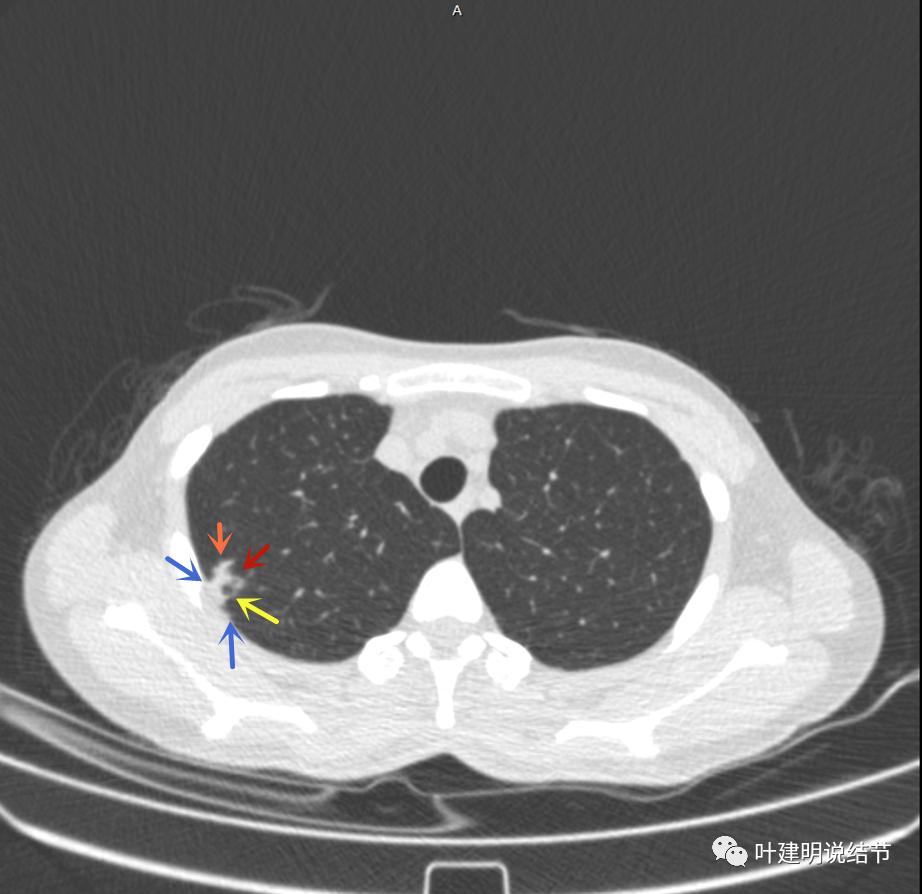

上面是她提供的病史资料,其中最重要的是PPD强阳性!其他主要看影像,我们先来看她2020年7月份的平扫片子(由于片子较多,详细展示是为了同道分析,我在影像特征描述上将只选取部分加以说明):

右肺尖偏实性结节(粉色箭头),邻近胸胸膜明显增厚不平,且广基附在胸壁上(蓝色箭头)

有卫星病灶(绿色箭头)

病灶有空洞(黄色箭头),主病灶边上见条索状高密度影(细红色箭头),邻近胸膜有粘连(蓝色箭头)